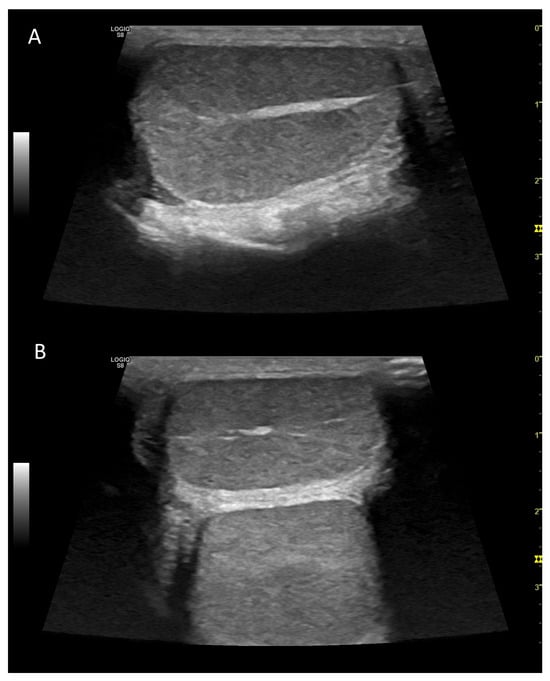

5. B-Flow